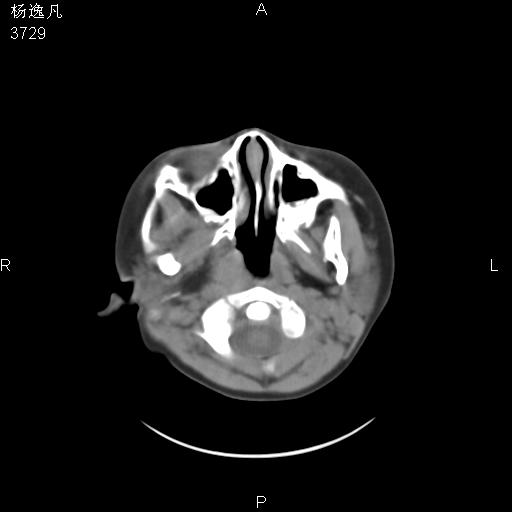

男性,5岁,面部受外伤,余无特殊

骨窗

鼻咽腺样体肥大。

鼻咽顶后变窄。顶后壁增厚,考虑腺样体肥大。其它未异常/

头颅ct平扫未见明确外伤性征象,右侧面部及颞部软组织肿胀,后鼻腔软组织影增大,增厚,鼻咽顶部变窄,考虑鼻咽腺样体增值肥厚。